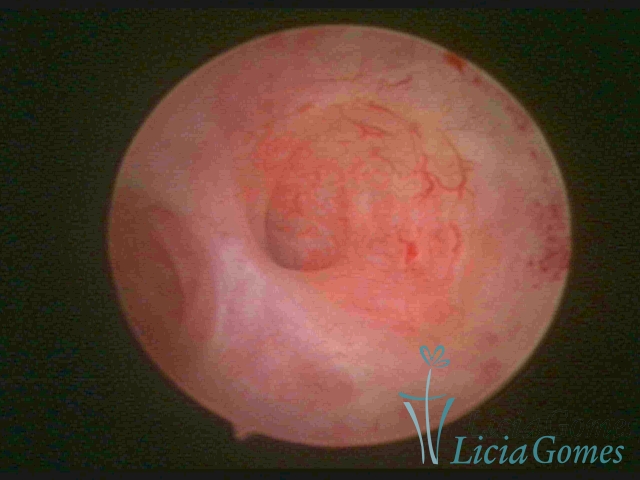

SINÉQUIA TIPO MUCOSA